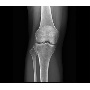

Klinikai esetek 3.